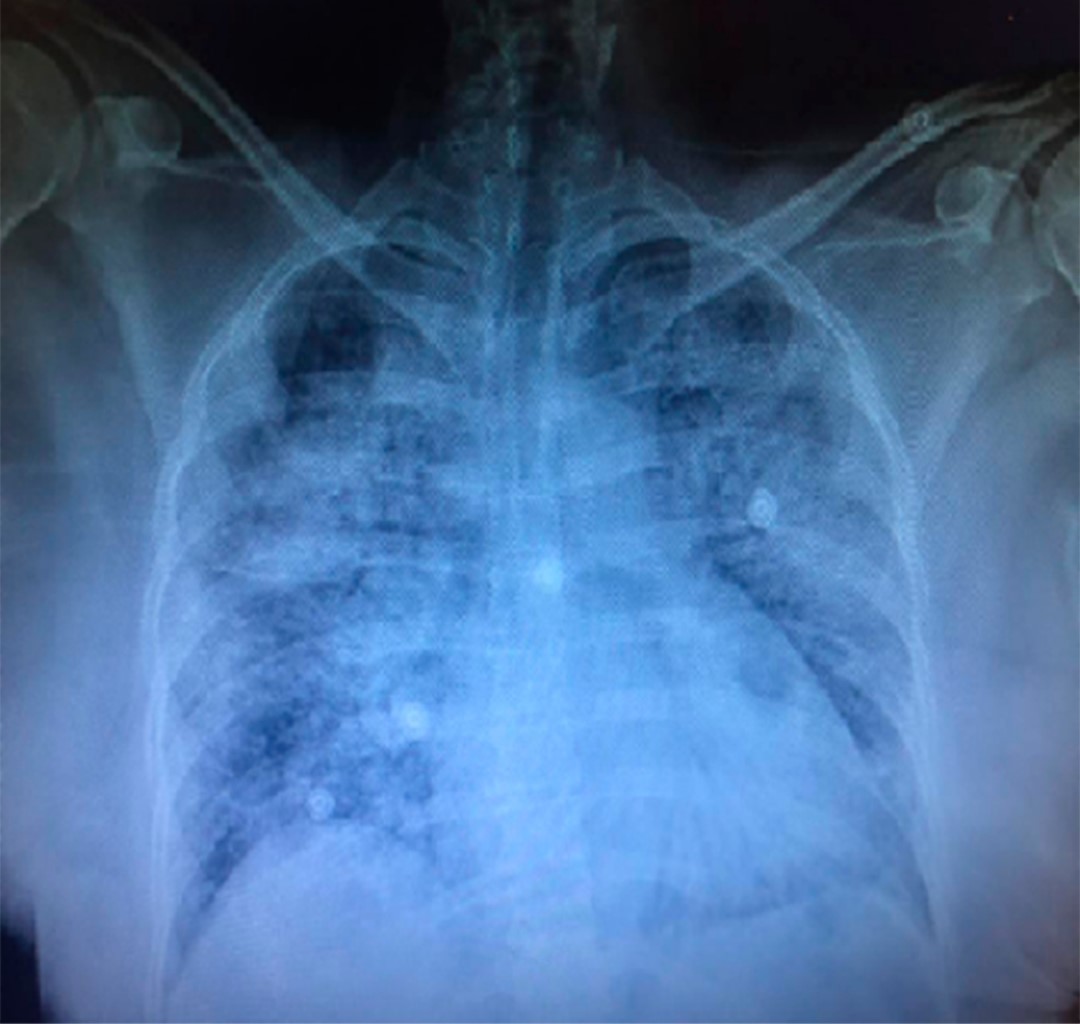

Es ingresada a la Unidad de Cuidados Intensivos (UCI) con los siguientes parámetros ventilatorios: modalidad control volumen con Vt 310 mL (6 mL/kg de peso predicho), PEEP 9 cmH2O, FiO2 70%, presión pico 27 cmH2O, presión media 15 cmH2O, presión meseta 23 cmH2O, driving pressure 14 cmH2O, saturación periférica 92%, manteniéndose en metas de oxigenación, sin requerimientos de vasopresor. La radiografía de tórax a su ingreso mostró infiltrados alveolares heterogéneos (Figura 1). Estudios de laboratorio: hemoglobina 10 g/dL, hematocrito 40.2%, leucocitos 10,000, plaquetas 412,000, neutrófilos 87.9%, linfocitos 8%, monocitos 3.9%, monocitos 0.2%, eosinófilos 0.0%, glucosa 100 mg/dL, BUN 27 mg/dL, creatinina 0.79 mg/dL, sodio 150 mmol/L, potasio 4.5 mmol/L, cloro 114 mmol/L. Gasometría arterial con pH 7.5, PaCO2 41, PaO2 59, HCO3 33.5, saturando 94%, relación PaO2/FiO2 84 mmHg. El tercer día de su ingreso a la UCI inicia con fiebre continua de 39 oC, se realiza toma de hemocultivos central y periféricos, cultivo de secreción bronquial, para posteriormente iniciar tratamiento a base de ceftazidima de 1 g IV cada 8 horas. La muestra de secreción bronquial fue obtenida mediante circuito cerrado, recolectada en un contenedor de plástico estéril y trasportada de manera inmediata al Servicio de Microbiología, donde se estableció que la muestra era idónea y cumplía con los requisitos de calidad establecidos para su análisis. Se realizó un examen en fresco reportando presencia de pseudohifas, cocos y moderada cantidad de protozoarios multiflagelados identificados como L. blattarum (Figura 2). Se solicita por parte del Servicio de Microbiología una segunda muestra donde se realizó una búsqueda intencionada de L. blattarum, documentándose de esta manera su presencia. Se realizó tinción de Gram reportando abundantes cocos Gran positivos agrupados en racimos; escasas levaduras y tinción de Ziehl-Neelsen que se reportó sin presencia de bacilos ácido alcohol resistentes. Se cambia esquema antimicrobiano a imipenem de 500 mg IV cada 6 horas, vancomicina de 1 g IV cada 12 horas y metronidazol de 500 mg IV cada 8 horas, se retira del tratamiento la ceftazidima. Se recaba cultivo de secreción bronquial que reporta moderado desarrollo Staphylococcus haemolyticus, Candida albicans y como observación hay presencia de L. blattarum, agregándose al tratamiento fluconazol de 200 mg IV cada 12 horas. El quinto día de estancia en la UCI persiste fiebre continua requiriendo inicio de vasopresor y presenta descenso progresivo de PaO2/FiO2. El séptimo día de estancia en la UCI la paciente presenta choque refractario y fallece.

Figura 1